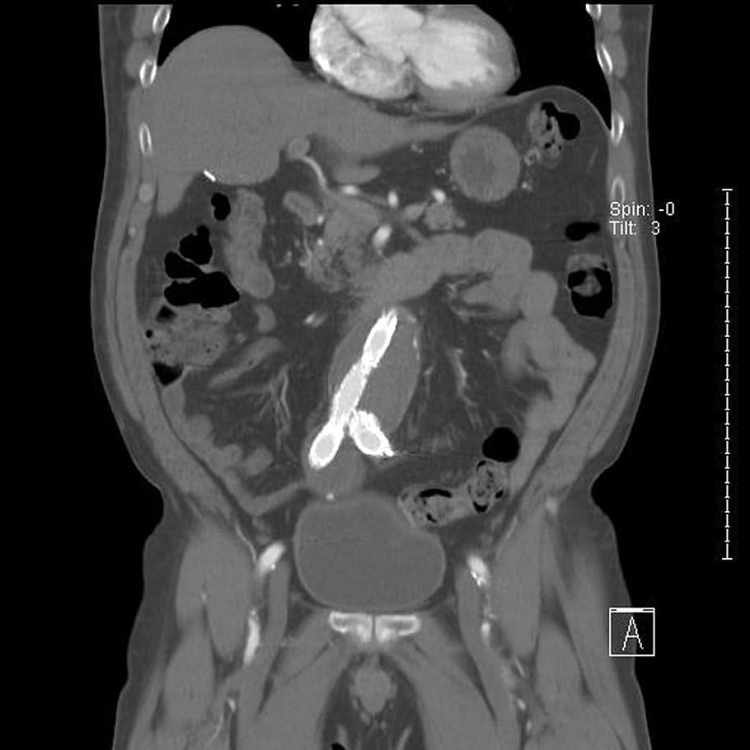

HD wallpaper: abdominal, aortic, aneurysm, stent, catscan, xray, medical - Wallpaper FlareUna radiografía de huesos es un examen de diagnóstico que utiliza radiación ionizante para obtener imágenes de los huesos del cuerpo. Es una de las técnicas de radiología más comunes y se utiliza para detectar fracturas, enfermedad ósea y artritis.